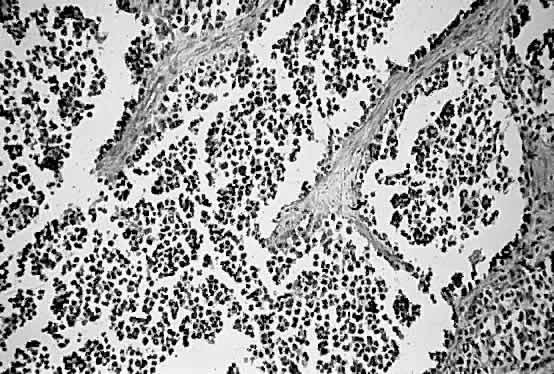

Alveolar RMS is the second most common type of RMS to involve the orbit and usually presents in the inferior quadrant.2,13,49 Its histologic pattern resembles the architecture of alveolar tissue of the lung (Fig. 4). The prognosis of alveolar RMS is considered worse than that of the embryonal variant.

Fig. 4. Alveolar pattern of rhabdomyosarcoma (H&E, × 90). (Courtesy of R. Jean Campbell, MB, ChB, Mayo Clinic, Rochester, Minnesota.)